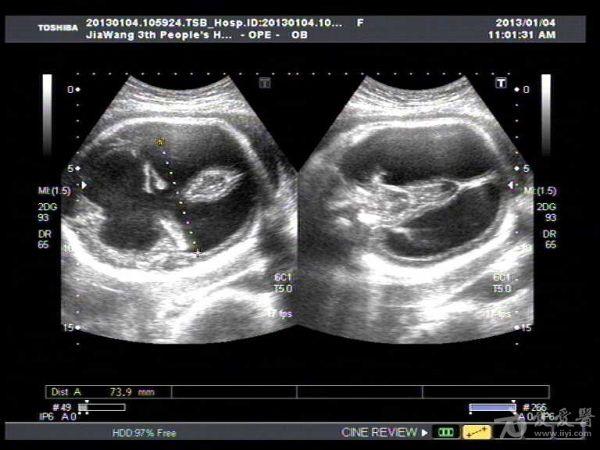

胎儿脑积水一例

此孕妇22岁,于孕六月来我院产检,可见胎儿侧脑室扩张积液约1.4Cm,遂告知小孩脑

积水,此孕妇接着去我们当地三甲医院检查,也被告知胎儿脑积水,建议引产。

此孕妇听信家人说吃核桃能补脑,吃了两个月核桃来来复查,脑积水更明显。